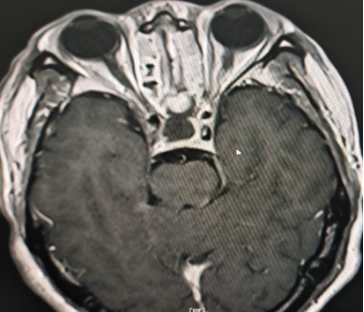

患者为69岁男性,因持续性头痛、视力下降伴双眼颞侧视野缺损前往阆中市人民医院神经外科就诊。经综合评估,结合内分泌检查及1.5T MRI动态增强扫描,确诊为垂体大腺瘤(2.0cm×1.7cm×1.7cm),肿瘤向上压迫视交叉,并伴有蝶窦气化不良。

针对该病例,垂体瘤多学科诊疗中心(MDT)多次组织讨论。鉴于传统开颅手术创伤大、恢复周期长,团队最终决定采用经鼻蝶内镜垂体瘤切除术。该微创技术通过鼻腔自然通道进入蝶鞍区切除肿瘤,具有创伤小、出血少、恢复快等优势。

手术过程中,团队在神经导航精准定位下,经鼻腔自然通道建立微创手术入路,完整切除肿瘤的同时最大限度保护正常组织结构,手术切口仅约2.0×1.5cm。术后患者恢复良好,无并发症发生,症状明显改善,目前已康复出院。